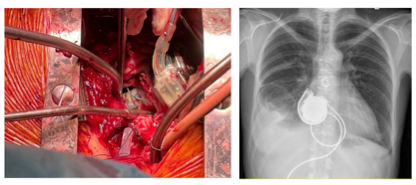

由于左心室腔较小,采用改良技术植入LVAD,通过左心房提供支持。通过右心房切开术,植入一根由20 mm Gore-Tex®插入式移植物制成的导管,一端缝入已形成的房间隔缺损,另一端用LVAD的缝合环缝入右前房壁。然后将HeartWare™HVAD™流入套管插入右心房壁的Gore-Tex®移植物中,并固定在缝合环上(图1)。修剪流出的移植物并与升主动脉吻合。三尖瓣后叶在相邻连合处缝合。左心耳未闭合。手术结束时,HVAD固定在胸腔右侧,然后胸腔闭合(图2和图3)。术后,患者在重症监护病房(ICU)接受护理,并于术后第二天(POD)拔管。患者于POD7转出ICU和高度依赖病房,于POD 21出院。

图1. 将HeartWare™HVAD™流入套管插入右心房壁的Gore-Tex®移植物中,并固定在缝合环上